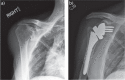

Since the introduction of reverse total shoulder arthroplasty (RTSA) in 1987 (in Europe) and 2004 (in the United States), the number of RTSAs performed annually has increased.Although the main indication for RTSA has been rotator cuff tears, indications have expanded to include several shoulder conditions, many of which involve dysfunction of the rotator cuff.RTSA complications have been reported to affect 19% to 68% of patients and include acromial fracture, haematoma, infection, instability, mechanical baseplate failure, neurological injury, periprosthetic fracture and scapular notching.Current controversies in RTSA include optimal baseplate positioning, humeral neck-shaft angle (135° versus 155°), glenosphere placement (medial, lateral or bony increased offset RTSA) and subscapularis repair.Improvements in prosthesis design, surgeon experience and clinical results will need to occur to optimize this treatment for many shoulder conditions. Cite this article: EFORT Open Rev 2018;3:58-69 DOI: 10.1302/2058-5241.3.170044.